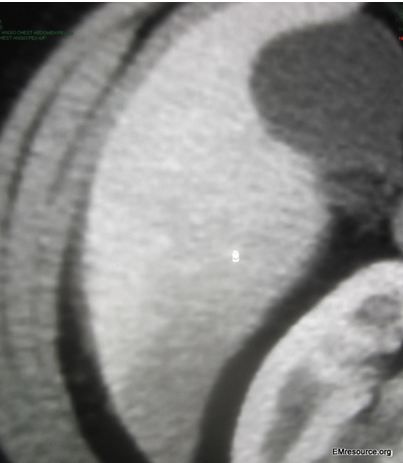

Figure 2. CT enlargement.

What is the finding? What is the diagnosis? ANSWER: The CT scan shows subtle increased flow to the liver capsule (see zoomed-in image in Figure 2). The diagnosis is Fitz-Hugh-Curtis syndrome.

Routine blood work including the CBC and even LFTs are usually completely normal. Inflammatory markers such as the erythrocyte sedimentation rate (ESR) and C-reactive protein (CRP) are often elevated. The D-dimer is also elevated in inflammatory conditions and should be checked when pain is pleuritic or accompanied by dyspnea as pulmonary embolism is often the main condition of the differential diagnosis of FHCS. Multiple imaging studies are often considered or ordered to rule out other conditions. The following tests will usually be read as normal if ordered: abdominal ultrasound, pelvic ultrasound, chest x-ray, CT chest, and CT abdomen. If the D-dimer is elevated a CT angiogram chest can rule out PE and may show subtle contrast enhancement around the liver, but beware you may have to request extra cuts to get that low and should talk to your radiologist as she/he will often not note this subtle finding unless they are looking for it.